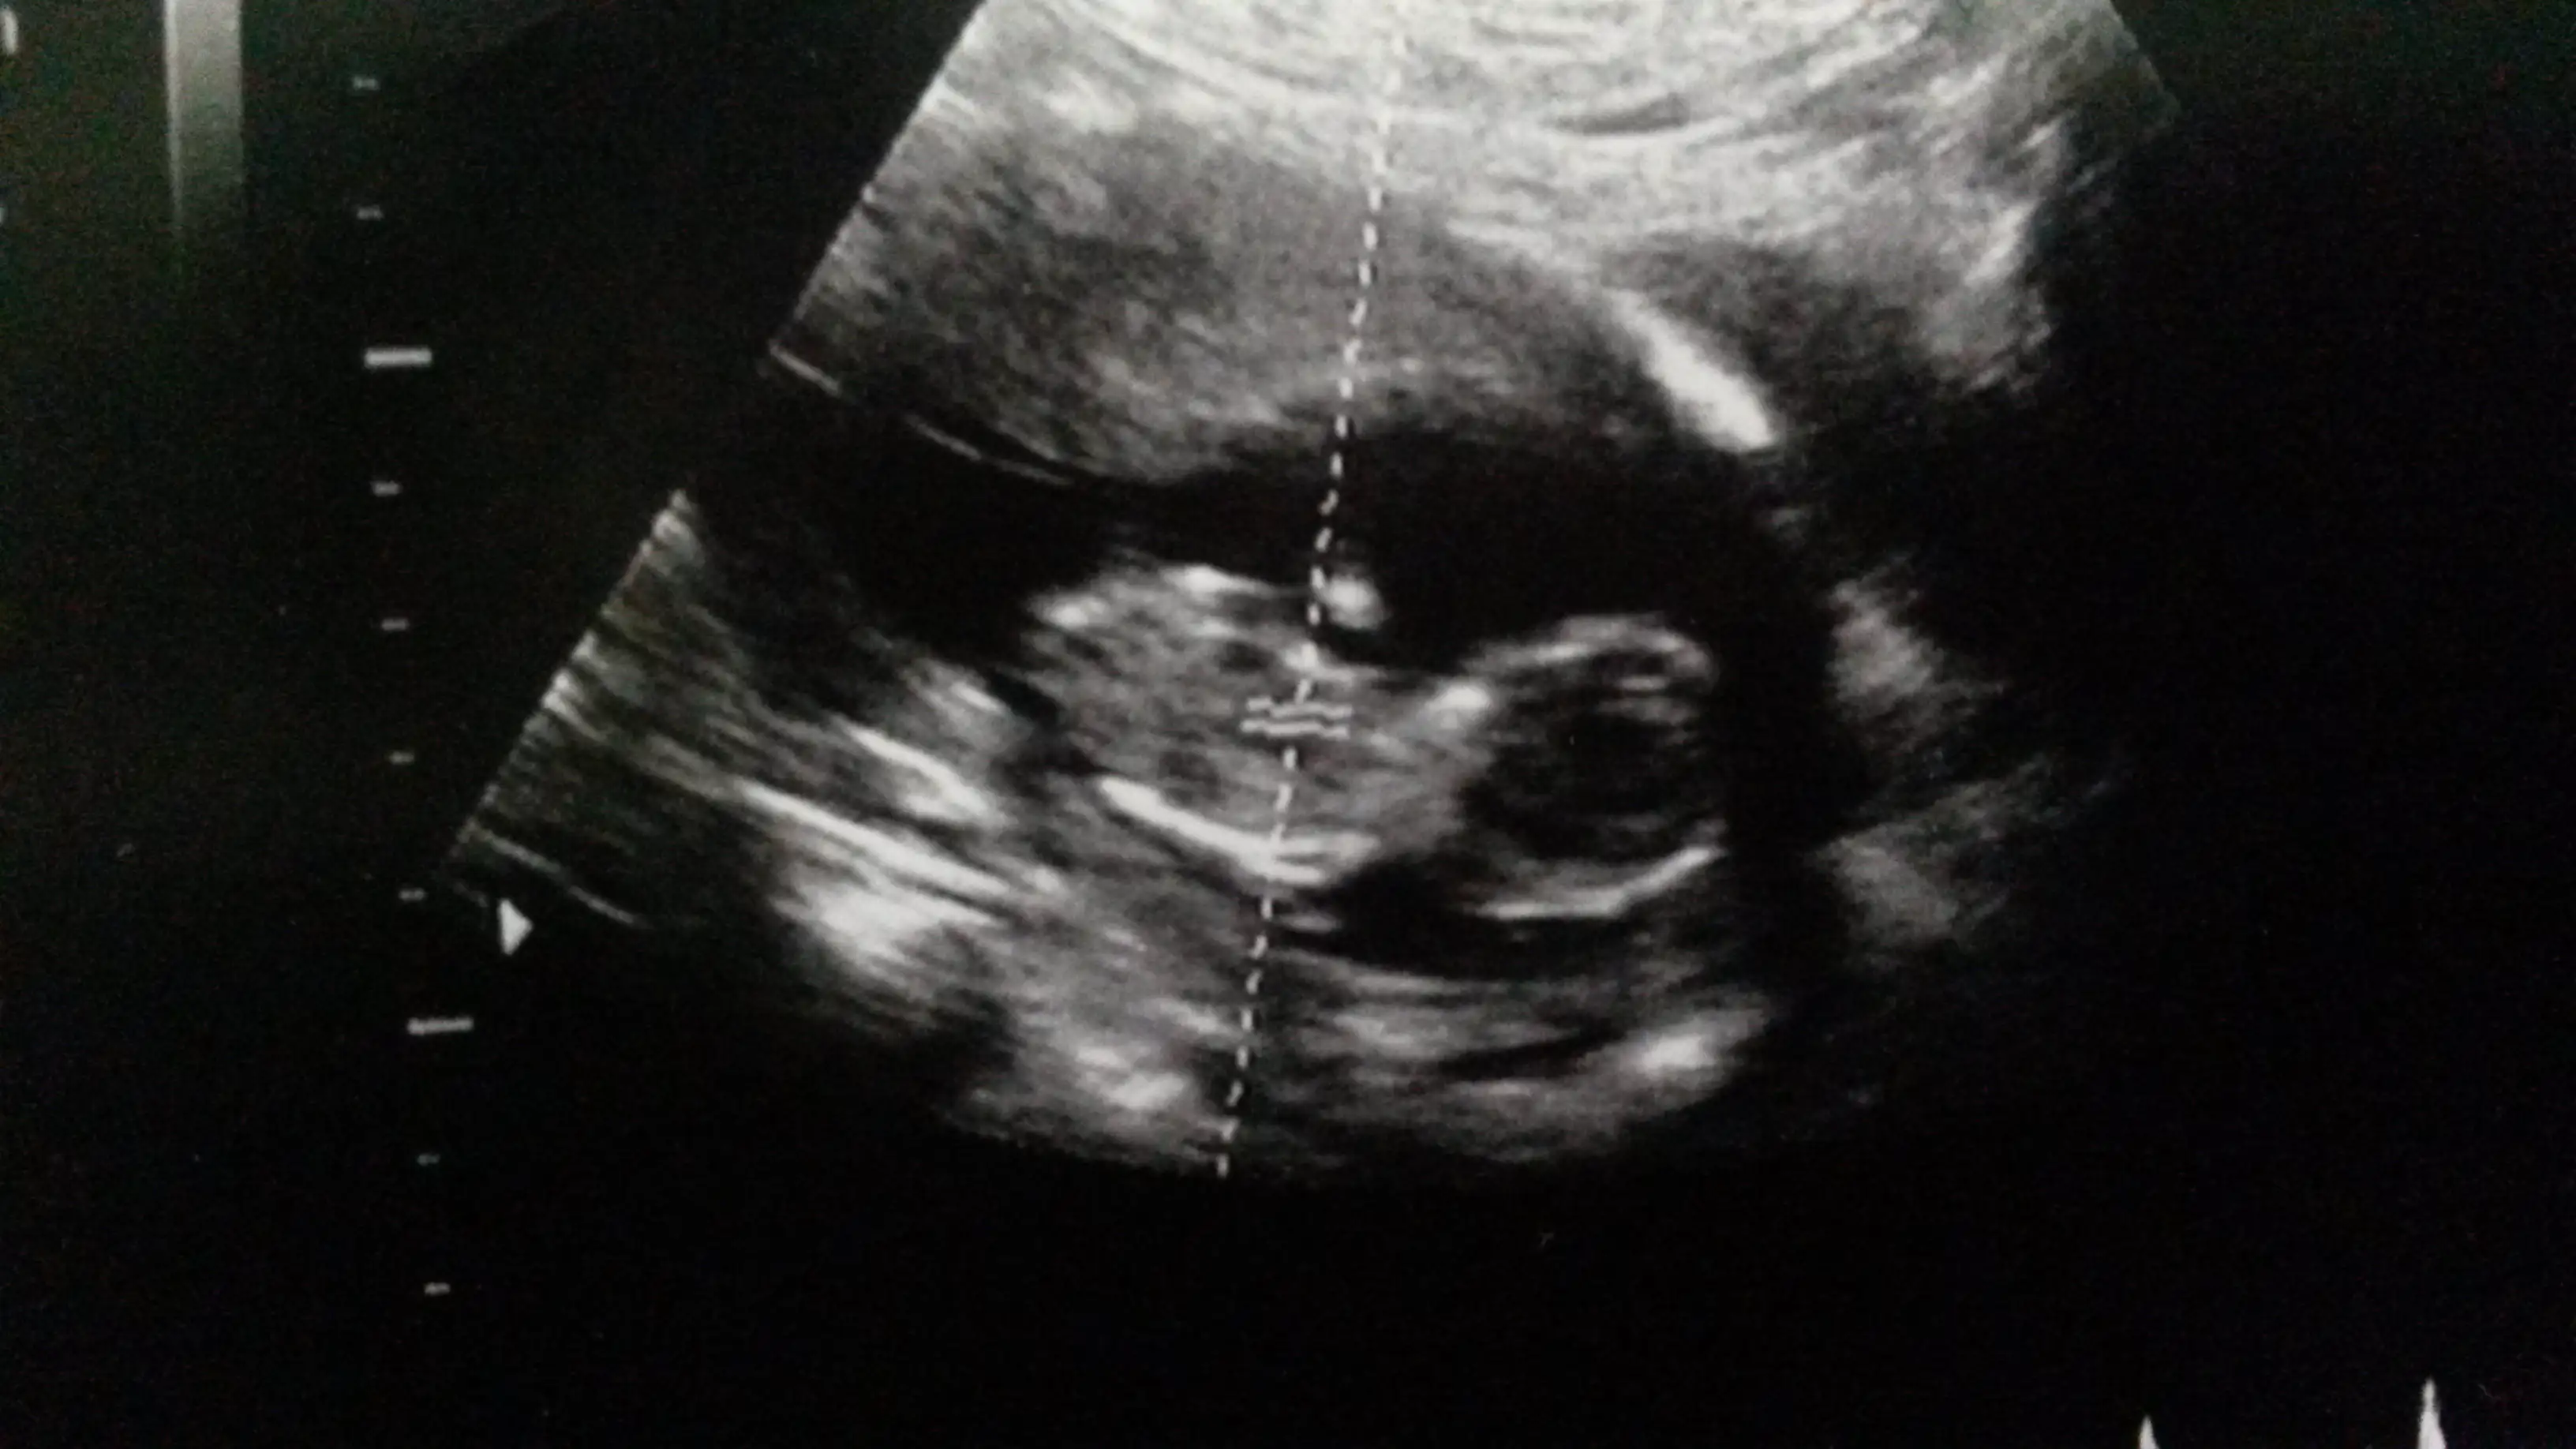

bizde 11+4 uz.bende bugun resim koydum ama kimse yorum yapmadi.benim dr da yorum yapmadi.gonlunden gecen,hayirlisi olsun ama kiza benzettim ki pek anlamiyorumEki Görüntüle 1311536

kızlar benim bebeğim 11 + 4 günlük. Doktor tahminde bulunmadı. Sizce bebeğimin cinsiyeti nedir yorum yapabilir misiniz?

yorumun ıcın sagol canım maalesef bende anlamıyorum bu nub işinden :)bizde 11+4 uz.bende bugun resim koydum ama kimse yorum yapmadi.benim dr da yorum yapmadi.gonlunden gecen,hayirlisi olsun ama kiza benzettim ki pek anlamiyorum![]()